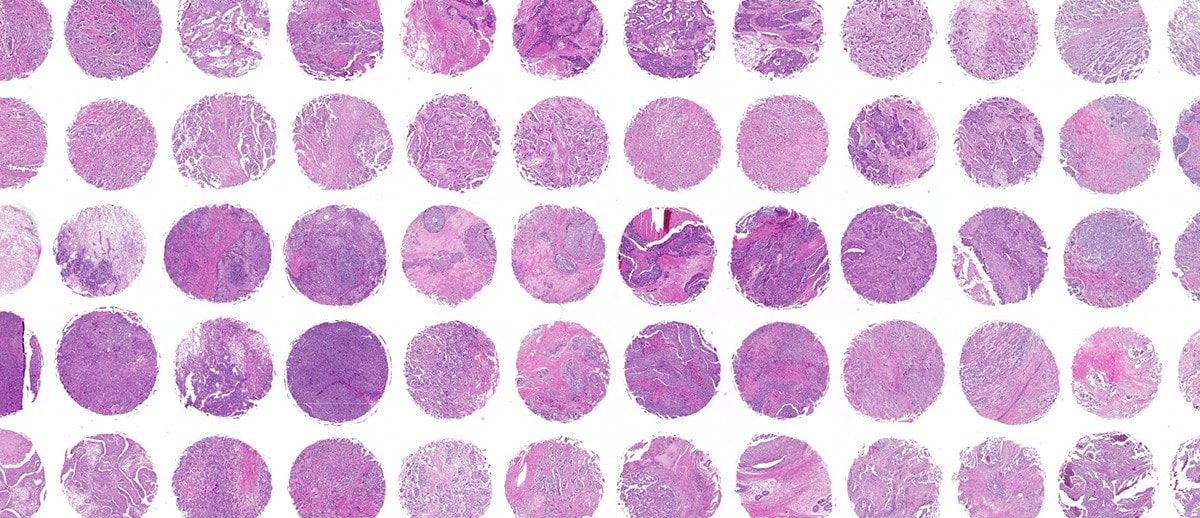

オールインワン蛍光顕微鏡 BZ-X800:解析アプリケーション 体験版, 大阪大学 創薬サイエンス研究支援拠点,

従来の半額の予算から導入できる!?オールインワン蛍光顕微鏡, 暗室不要でクリアな蛍光観察。ウェルすべてを一括解析できる蛍光,

暗室不要でクリアな蛍光観察。ウェルすべてを一括解析できる蛍光, オールインワン蛍光顕微鏡 BZ-X シリーズ | キーエンス,